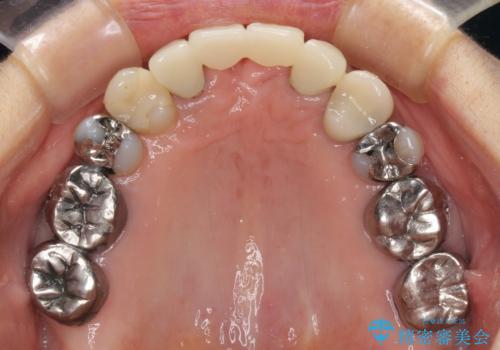

話しにくく腫れやすい前歯のブリッジ 使用感の良いオールセラミックブリッジに

- 矯正治療を行った歯科医院で装着した前歯の仮歯が不快とのことで来院された患者様です。

仮歯自体はとても綺麗でしたが、2本の歯が欠損している部分に上唇小帯が入り込んでいたため、歯肉形成を行った上で仮歯を調整し、オールセラミックブリッジを装着することとしました。

他にも治療が必要な歯があったため、合わせてセラミッククラウンやセラミックインレーで治療することとしました。

上唇小帯を切除したことで、ブリッジのダミー部分に触れて腫れていた歯肉は健全な状態になりました。

隙間もなくなったことで話す際の空気の漏れや、ものが挟まることもなくなりました。